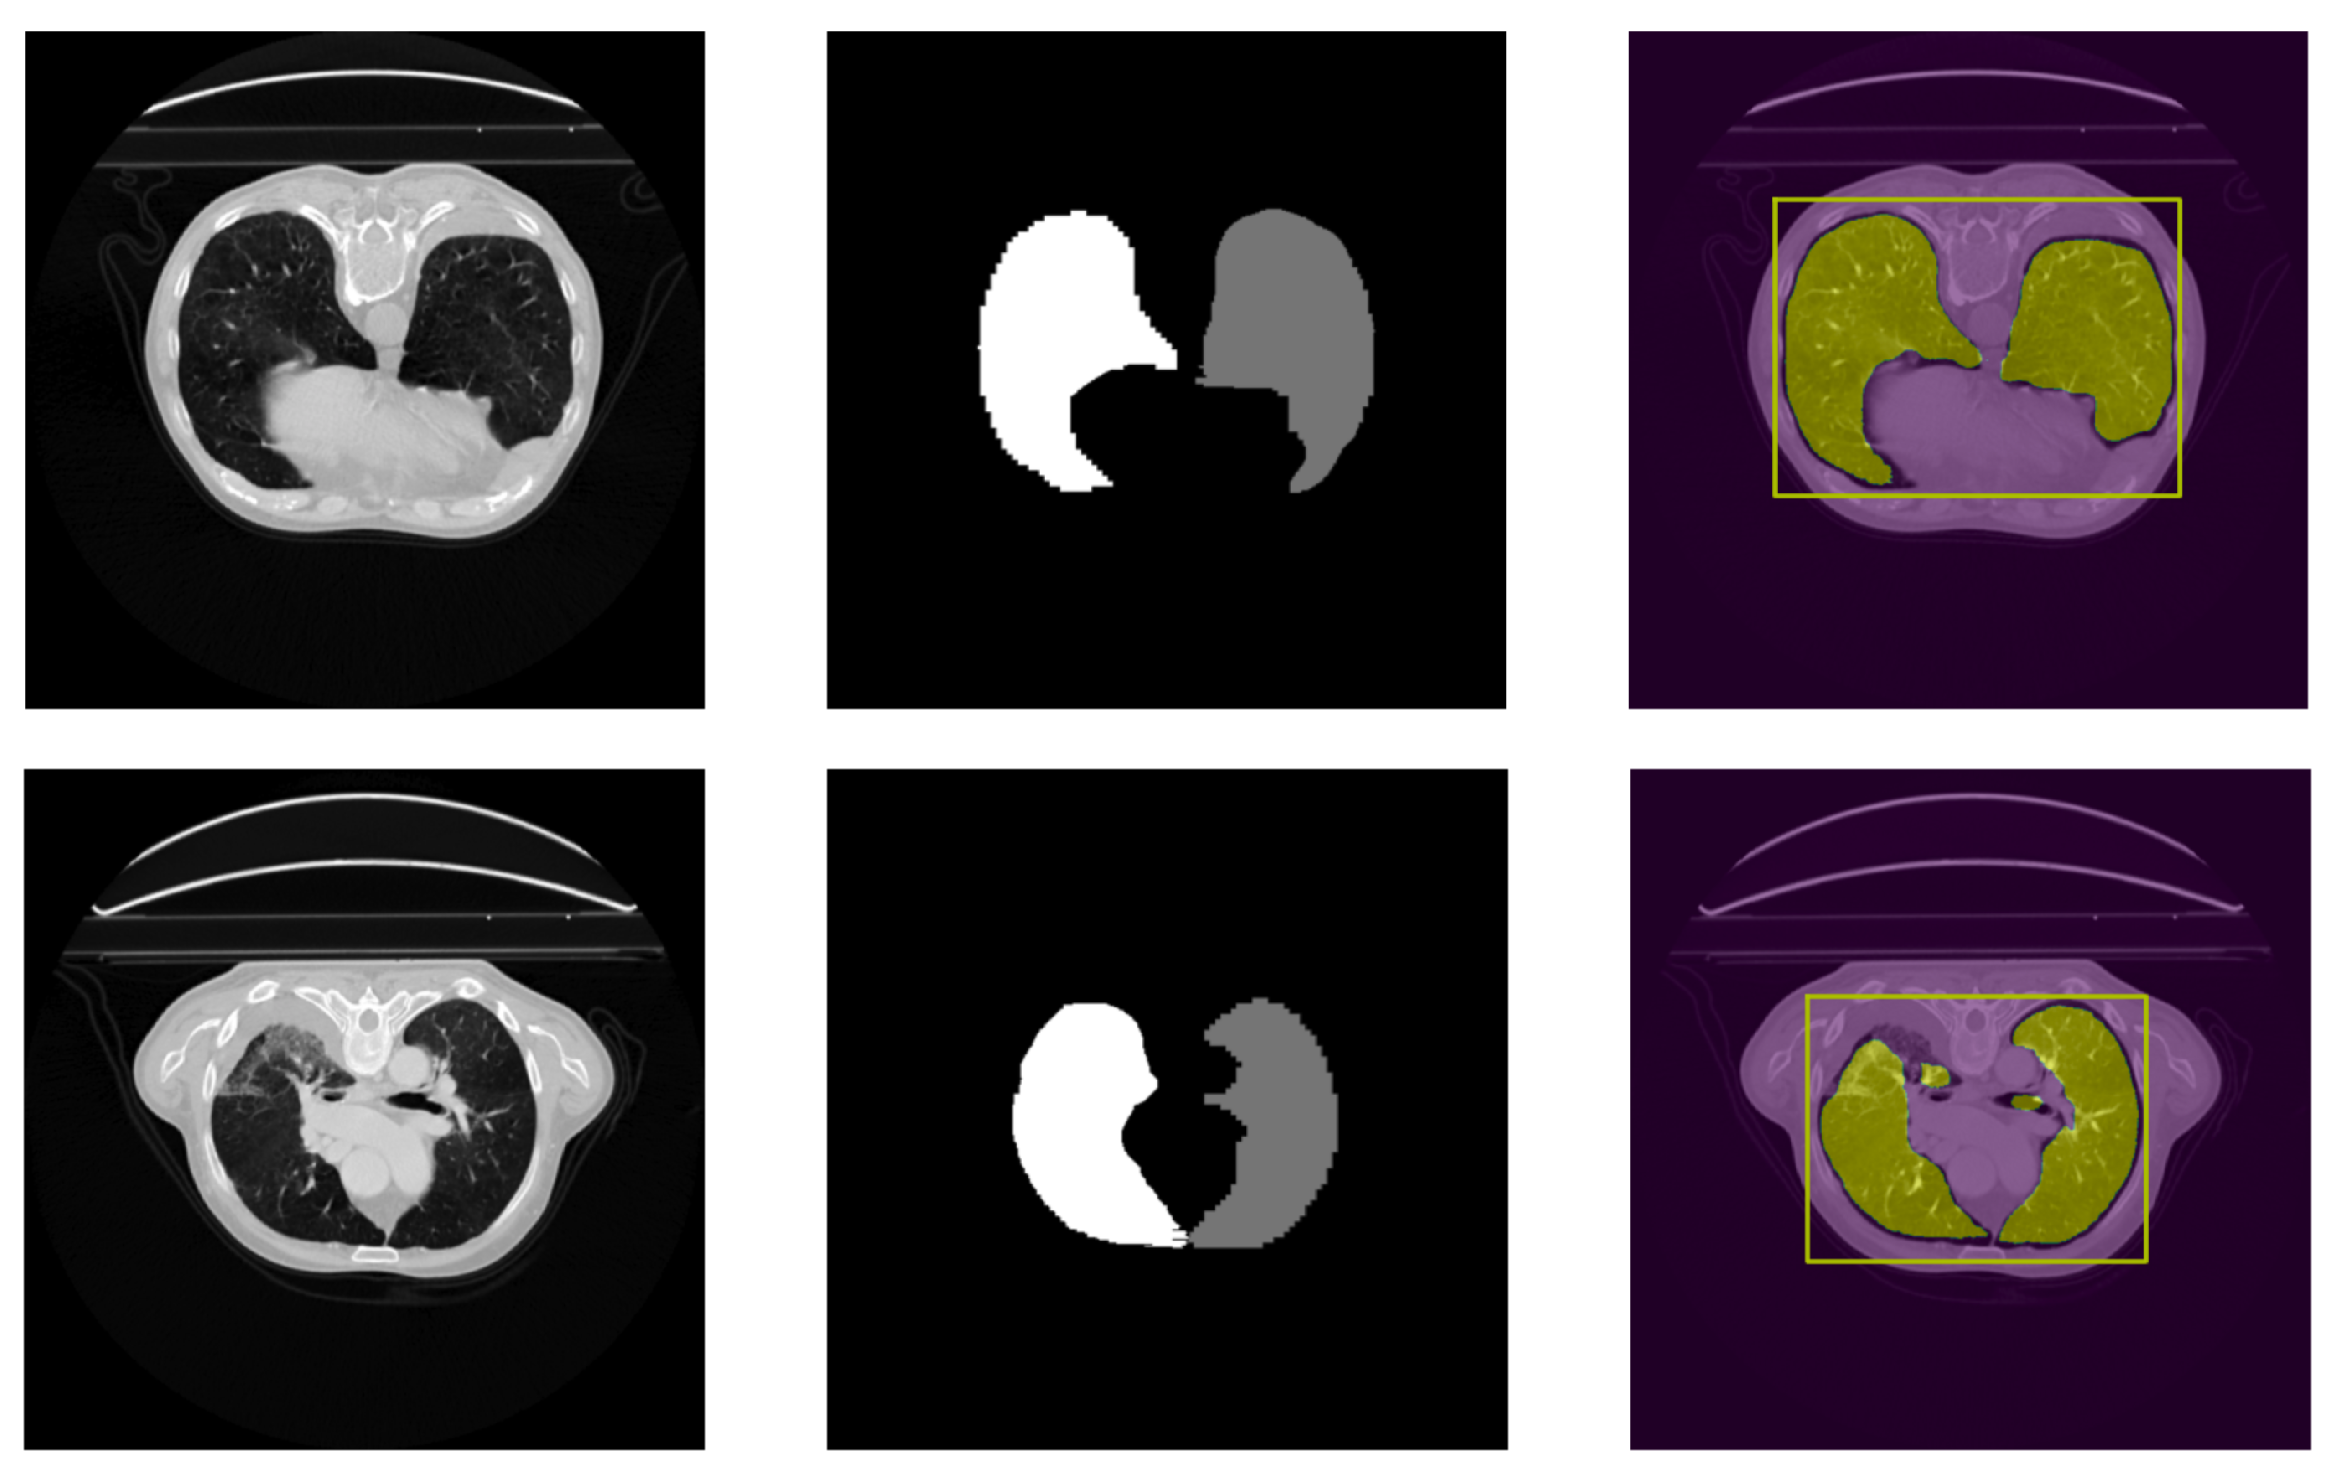

4.2. Qualitative Results

4.3. External Validation on PleThora Dataset

- Morphological Characteristics: The presence of anatomical structures with geometric characteristics similar to irregular or hidden ROI can generate segmentation errors. The model may incorrectly interpret these formations as potential ROI. In advanced lung disease, ROI such as tumors or affected lung parenchyma can exhibit highly irregular shapes and may be partially obscured or hidden by surrounding diseased tissue, pleural effusions, or consolidation, as frequently observed in the PleThora dataset. SALM, trained primarily on datasets with relatively well-defined ROI like LUNA16, may struggle to accurately delineate these highly irregular and poorly defined ROI in advanced pathological cases. The model’s reliance on shape features learned from less complex examples might lead to under-segmentation or inaccurate boundary delineation when confronted with the complex and atypical morphologies characteristic of advanced lung pathologies. This is further compounded by the fact that, in diseased lungs, the contrast between the ROI and the surrounding abnormal tissue may be reduced, making morphological differentiation even more challenging for the model.